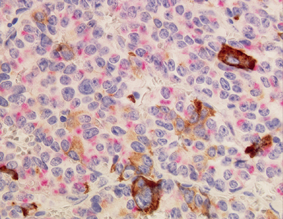

成長ホルモンの高い先端肥大症の患者さんからとった下垂体腺腫の免疫組織染色です。左はHE染色という普通のもの。右図ではピンクでプロラクチン(PRL)を,茶色で成長ホルモン(GH)を染色していますが,2種類のホルモンを作る腫瘍はめずらしくありません。